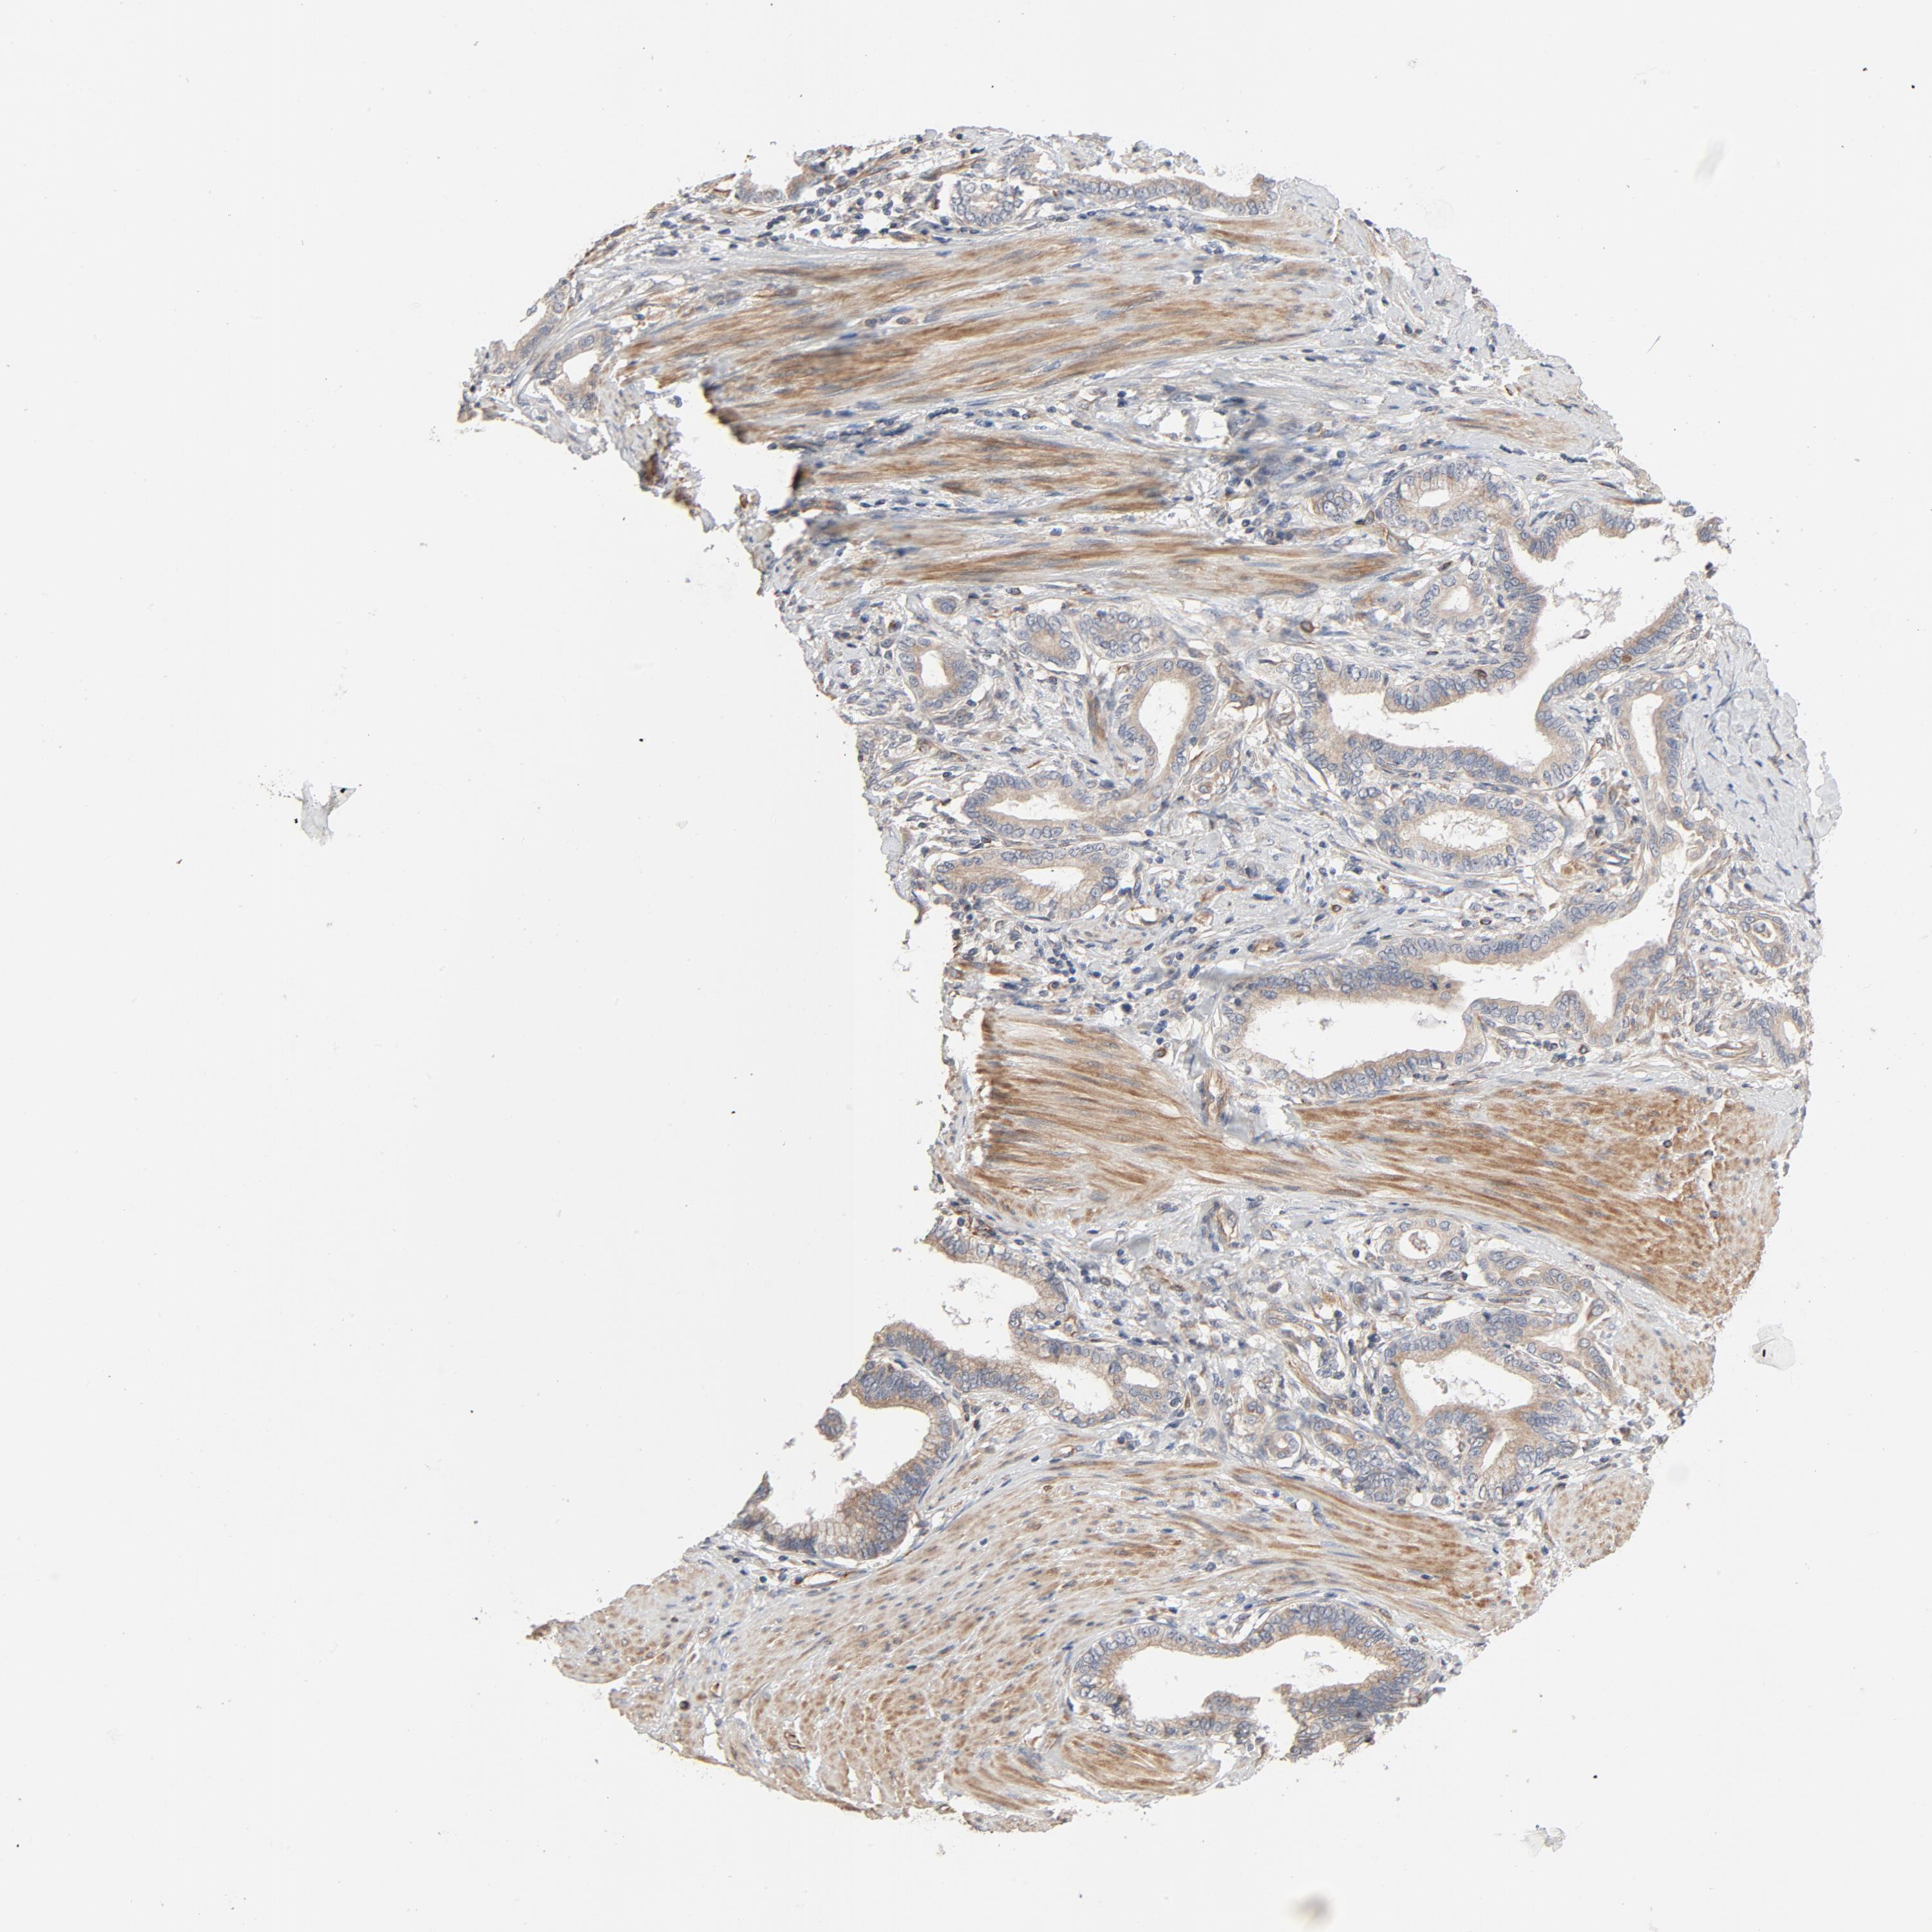

PANCREATIC CANCER - Protein expressioni

A mouse-over function shows sample information and annotation data. Click on an image to view it in a full screen mode. Samples can be filtered based on level of antibody staining by selecting one or several of the following categories: high, medium, low and not detected. The assay and annotation is described here.

Note that samples used for immunohistochemistry by the Human Protein Atlas do not correspond to samples in the TCGA dataset.

Antibody stainingi

Antibody staining in the annotated cell types in the current human tissue is reported as not detected, low, medium, or high, based on conventional immunohistochemistry profiling in selected tissues. This score is based on the combination of the staining intensity and fraction of stained cells.

Each image is clickable and will lead to virtual microscopy that enables deeper exploration of all samples and also displays staining intensity scores, fraction scores and subcellular localization as well as patient and tissue information for each sample.

Antibody HPA003747

Antibody HPA019769

Staining

High

Medium

Low

Not detected

Intensity

Strong

Moderate

Weak

Negative

Quantity

>75%

75%-25%

<25%

None

Location

Nuclear

Cytoplasmic/membranous

Cytoplasmic/membranous,nuclear

Adenocarcinoma, NOS

Adenocarcinoma, metastatic, NOS